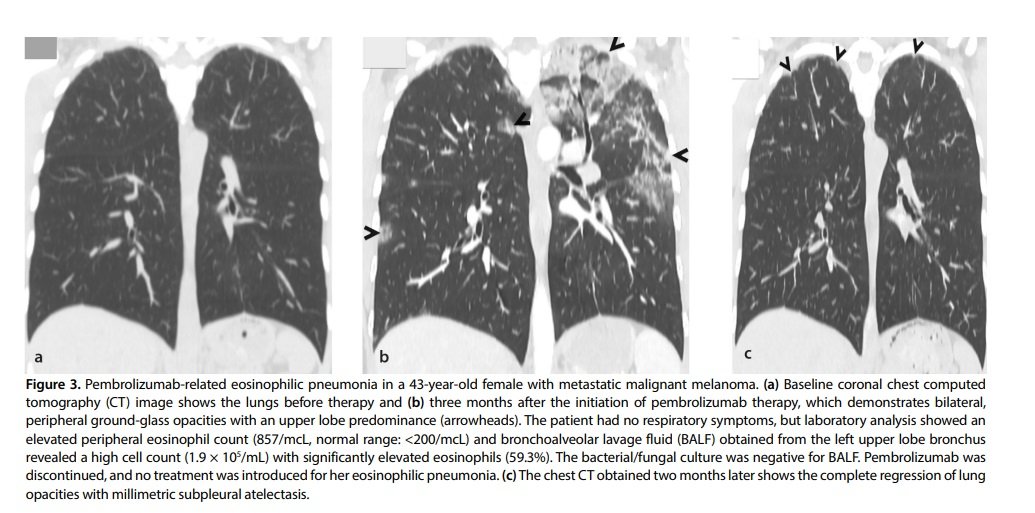

Although eosinophilic pneumonia (EP) can be present in similar imaging findings with an OP pattern, EP is characterized by peripheral band-like opacities and predominance in the upper lobes